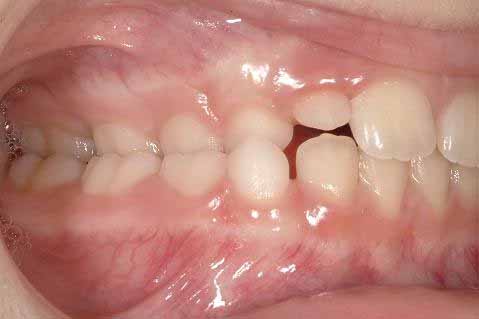

片側性交叉咬合は、10%以上の有病率で、交叉咬合の中で最もよく見られる不正咬合のひとつです。片側性交叉咬合とは、上顎と下顎を噛み合わせた時に、上顎と下顎の幅が一致しないことを意味します(画像1)。これは、咬合時に下顎が横方向にずれること(いわゆる反対咬合)を意味し、片側性交叉咬合と正中線からのずれを引き起こします。